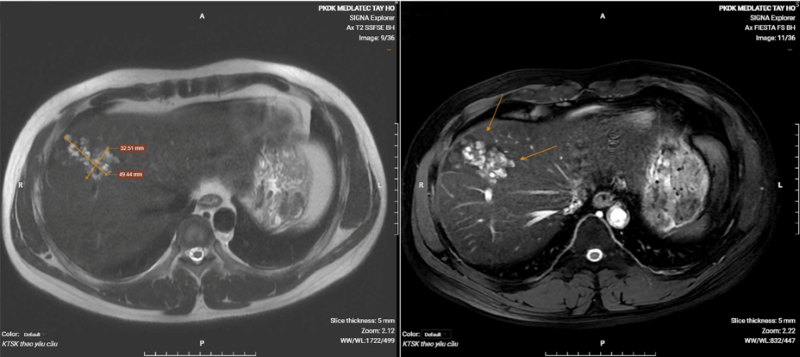

Anh L.T.N. (41 tuổi, Hà Nội) đến thăm khám sức khỏe định kỳ phát hiện kết quả chụp CT ổ bụng ghi nhận hình ảnh đám tổn thương tại phân thùy trước sát bao gan, kích thước khoảng 35x54mm, dạng hoại tử dịch hóa nhiều ổ - nghi ngờ tổn thương gan do sán lá gan. Xét nghiệm sàng lọc các bệnh lý ký sinh trùng cho kết quả dương tính với sán lá gan lớn.

Hình ảnh chụp CT ổ bụng của bệnh nhân phát hiện tổn thương